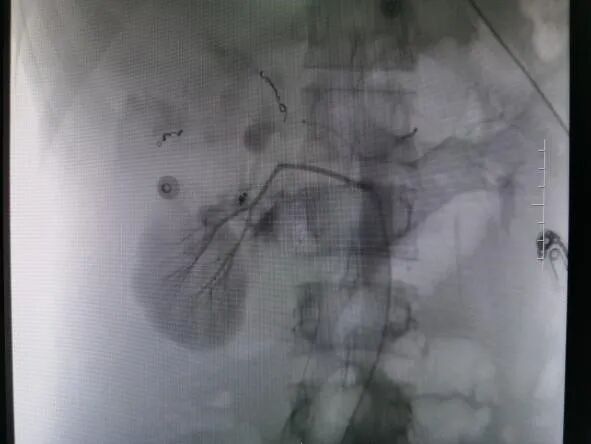

术后DSA造影图

救治方案明确后,患者立即被推入了手术室,在邓文军总监的指挥下,一场惊心动魄、紧张有序的手术开始了。各专科主任严阵以待,在院待命,随时做好开腹手术准备。介入手术由影像中心副主任兼介入组组长吴继雄主任医师亲自主刀,手术过程顺利,术中造影找到右肾脏有几处明显的活动性出血点,肝脏也有两处活动性出血点,给予及时栓塞止血后,再次造影无明显出血。整个手术仅约一个小时,刀口仅针眼大小,术中病人情况稳定,失血量不到10ml,患者成功脱离生命危险,术后被送入ICU密切观察诊治。病情平稳后转入普通病房,经过后续治疗目前该患者已经平安出院,出院时状态良好已经能自行走路。